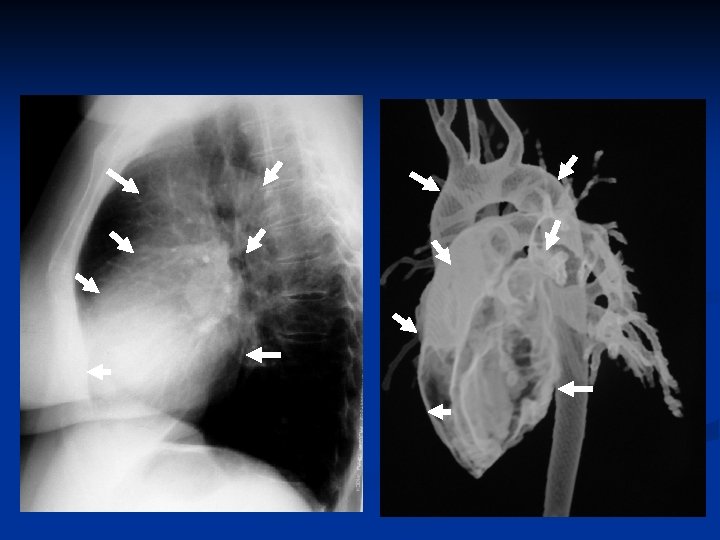

Radiograma em Perfil

Interpretação do Radiograma tórax - Perfil Sinal da coluna v coluna dorsal mais visível de cima para baixo v maior quantidade de músculos na parte superior do tórax v menor volume de ar pulmonar nesta região